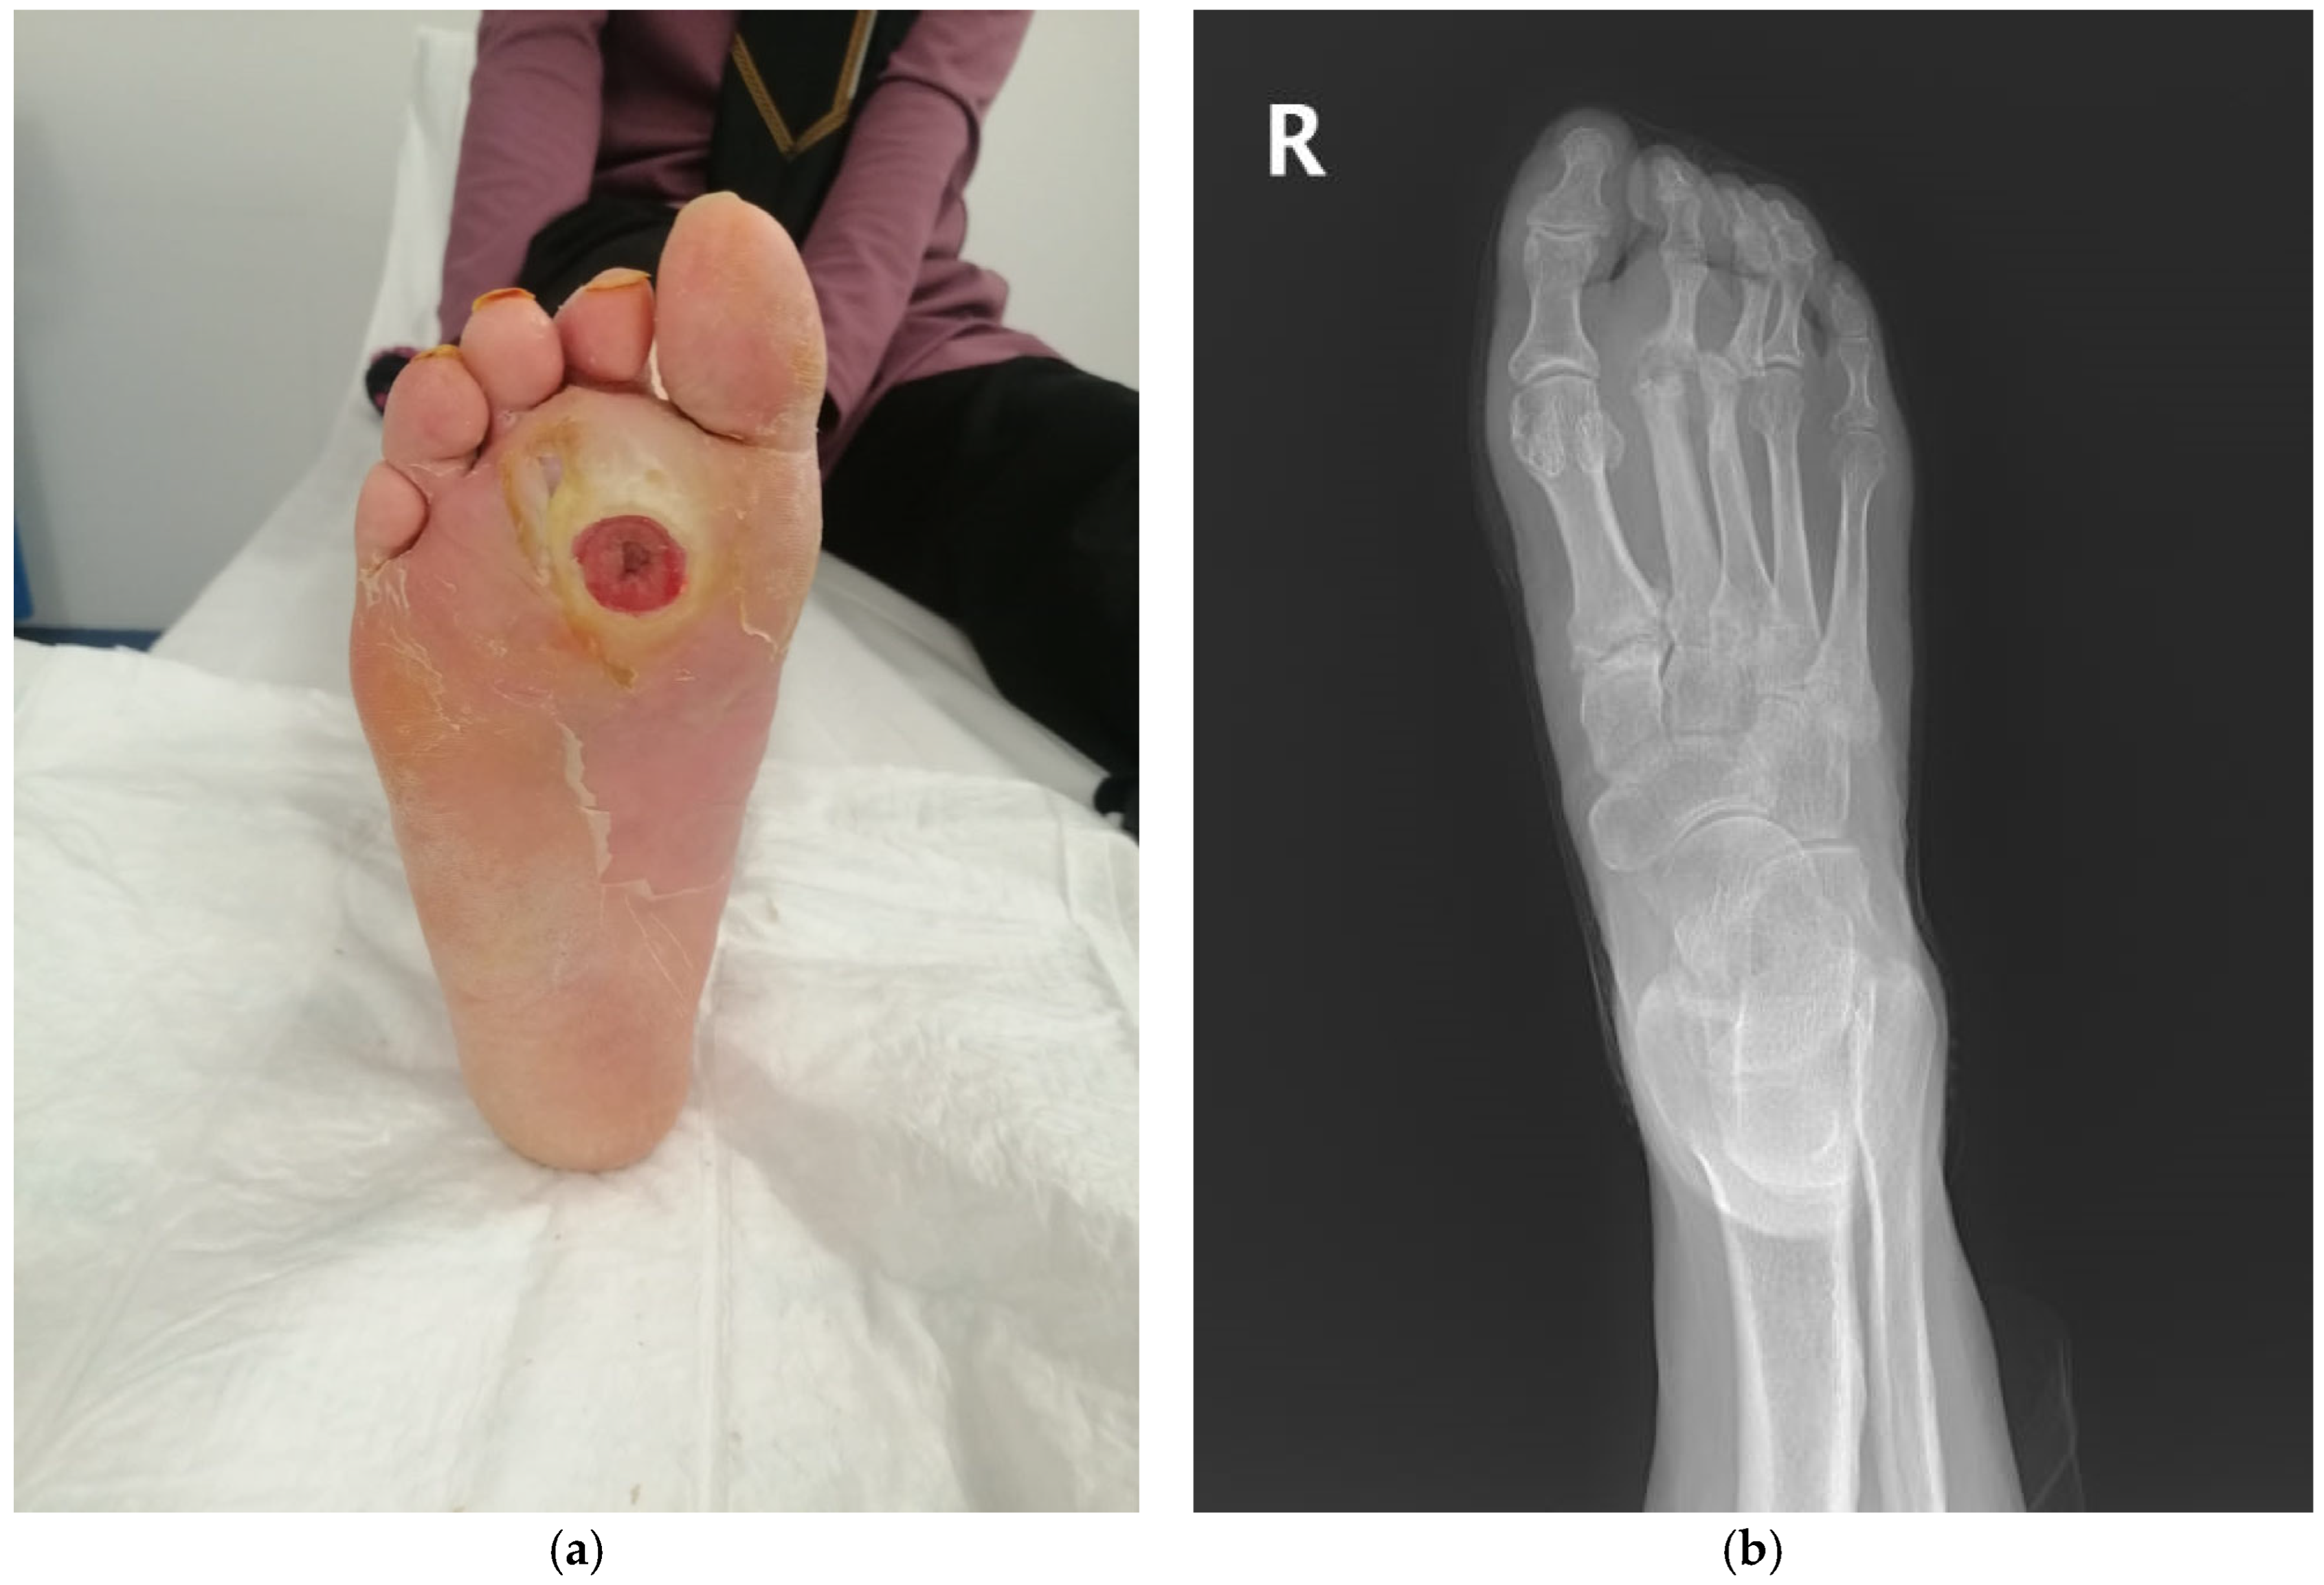

- Positive probe-to-bone (PTB) test (defined as palpable bone through the ulcer using a sterile blunt metal probe);

- Underwent surgical intervention (debridement or amputation) during which deep tissue and bone culture samples were intended to be collected simultaneously;

2.3. Specimen Collection